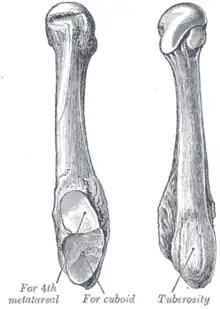

Comme pour les quatre autres os métatarsiens, il peut être divisé en trois parties : la base, le corps et la tête.

Sa base est aplatie de haut en bas et projette en arrière, en dehors et en bas une apophyse : la tubérosité du cinquième os métatarsien qui donne insertion au tendon du muscle court fibulaire. Elle est reliée à la tubérosité du calcanéum par une bande du fascia plantaire.

En arrière une surface articulaire triangulaire coupée obliquement dans le sens transversal s'articule avec le cuboïde. Médialement elle présente une facette articulaire pour le quatrième métatarsien.